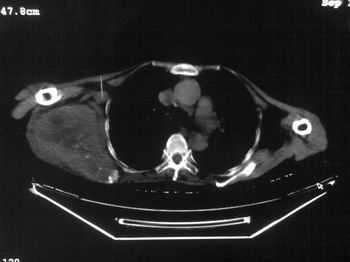

以下是引用zhangxu5888在2007-9-11 16:25:00的发言:[br]有侧肩胛骨溶骨性破坏且见软组织成分,增强软组织强化明显,中央见低密度坏死区!根据病史10年,考虑良性肿瘤恶性变!性质待定!

以下是引用老爱克斯新网客在2007-9-11 18:22:00的发言:[br]应该是良性肿瘤恶变,但因晚期破坏严重不能见到原来肿瘤征象无法判断,